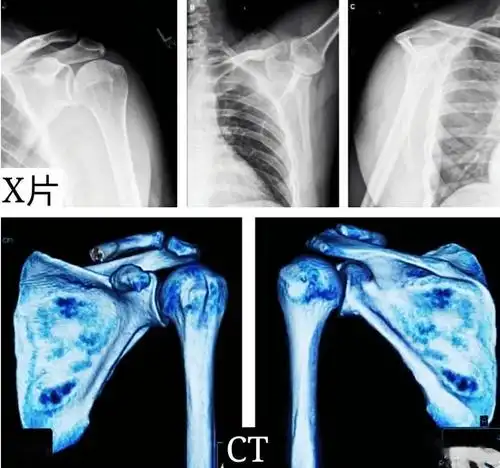

corr临床对照研究:移位性肩胛骨骨折的非手术与手术治疗效果相似